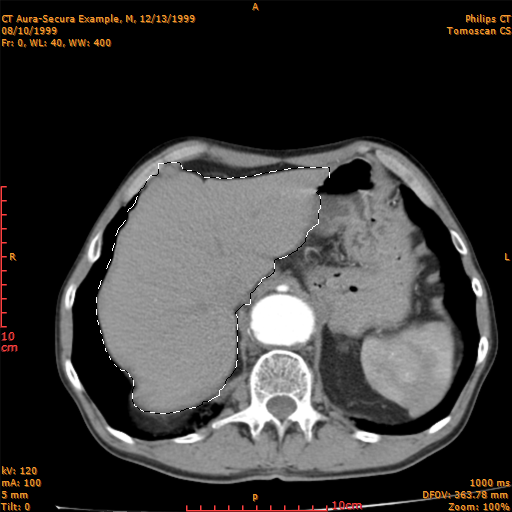

Work with selections, measure area and volume, make statistical analysis of a selected area

There are seven selection tools available in the program: the Rectangle tool, the Polygon tool, the Circle tool, the Ellipse tool, the Free Hand tool, the Magic Wand tool, and the Eyedropper tool. With these tools you can select a portion of an image. With any of these tools you can create a new selection, add to an existing selection, subtract from a selection, or select an area intersected by other selections. The selected area is marked with a dashed, rotated, black and white line. You can use the selection tools to measure area and volume of the selected portion or to make a statistical analysis (maximum, minimum and mean values standard deviation etc.). You can export the selected area to a text file (in form of X position, Y position, Value) for further analysis with other programs (e.g. MATLAB or ANSYS).

The free hand tool lets you draw freehand segments of a selection border.

Magic Wand:

The magic wand tool lets you select a continuous area of similar intensity without having to trace its outline.